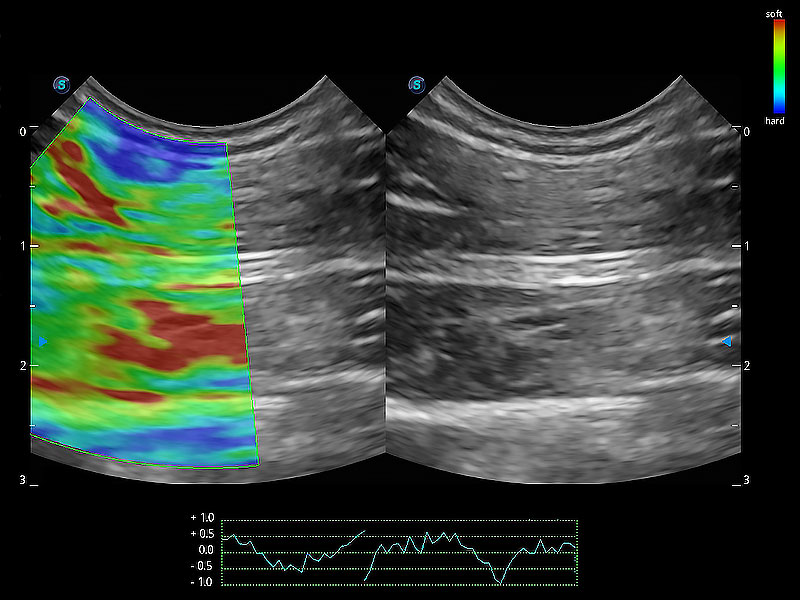

极大提升超低速微细血流的检出能力,同时更精准地滤除软组织和超声信号,为兽用医生提供以往无法通过常规血流获得的疾病诊断信息。

操作简便,无需高频度外力作用即可真实反映组织的形变,快速评估肿瘤良恶性。